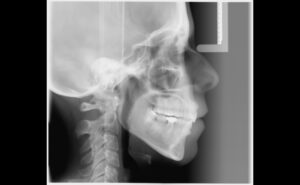

• Tratamiento ortopédico mediante aparatos de ortodoncia.